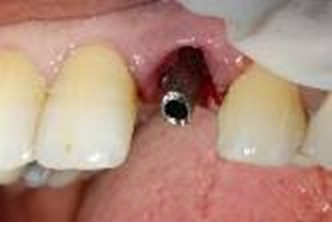

The surgical guide was placed and fixed (Figure 7) and we began the drilling sequence, to place a biotech 3,6/12 implant (Figure 8).

Figure 7. Placement of the surgical guide

Figure 8. Drilling sequence

After implant placement (Figure 9), the primary stability of the implant was satisfactory (greater than 35N), the provisional abutment was fixed (Figure 10) and a post-operative retroalveolar radiograph was taken for radiological control of the implant and adaptation of the provisional abutment (Figure 11).